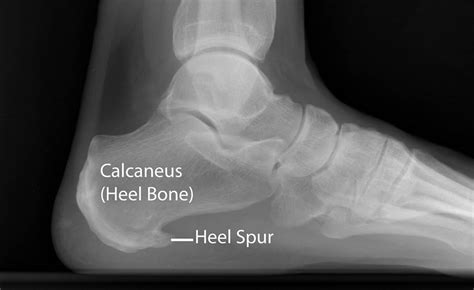

A spur on heel bone is essentially a calcium deposit that causes a bony protrusion on the underside of the heel bone. Over a period of several months, these calcium deposits build up, eventually forming a visible or palpable bony growth. These spurs are often identified through X-rays and are frequently associated with chronic inflammation in the soft tissue of the foot.

It is important to clarify a common misconception: the spur itself is not always the primary source of pain. Often, the pain stems from the underlying condition that caused the spur to develop, such as chronic inflammation of the plantar fascia—the thick band of tissue that connects your heel bone to your toes. This condition is known as plantar fasciitis. When the plantar fascia is strained, it can cause small tears and inflammation, eventually leading the body to deposit calcium to protect the area, which results in the formation of a heel spur.